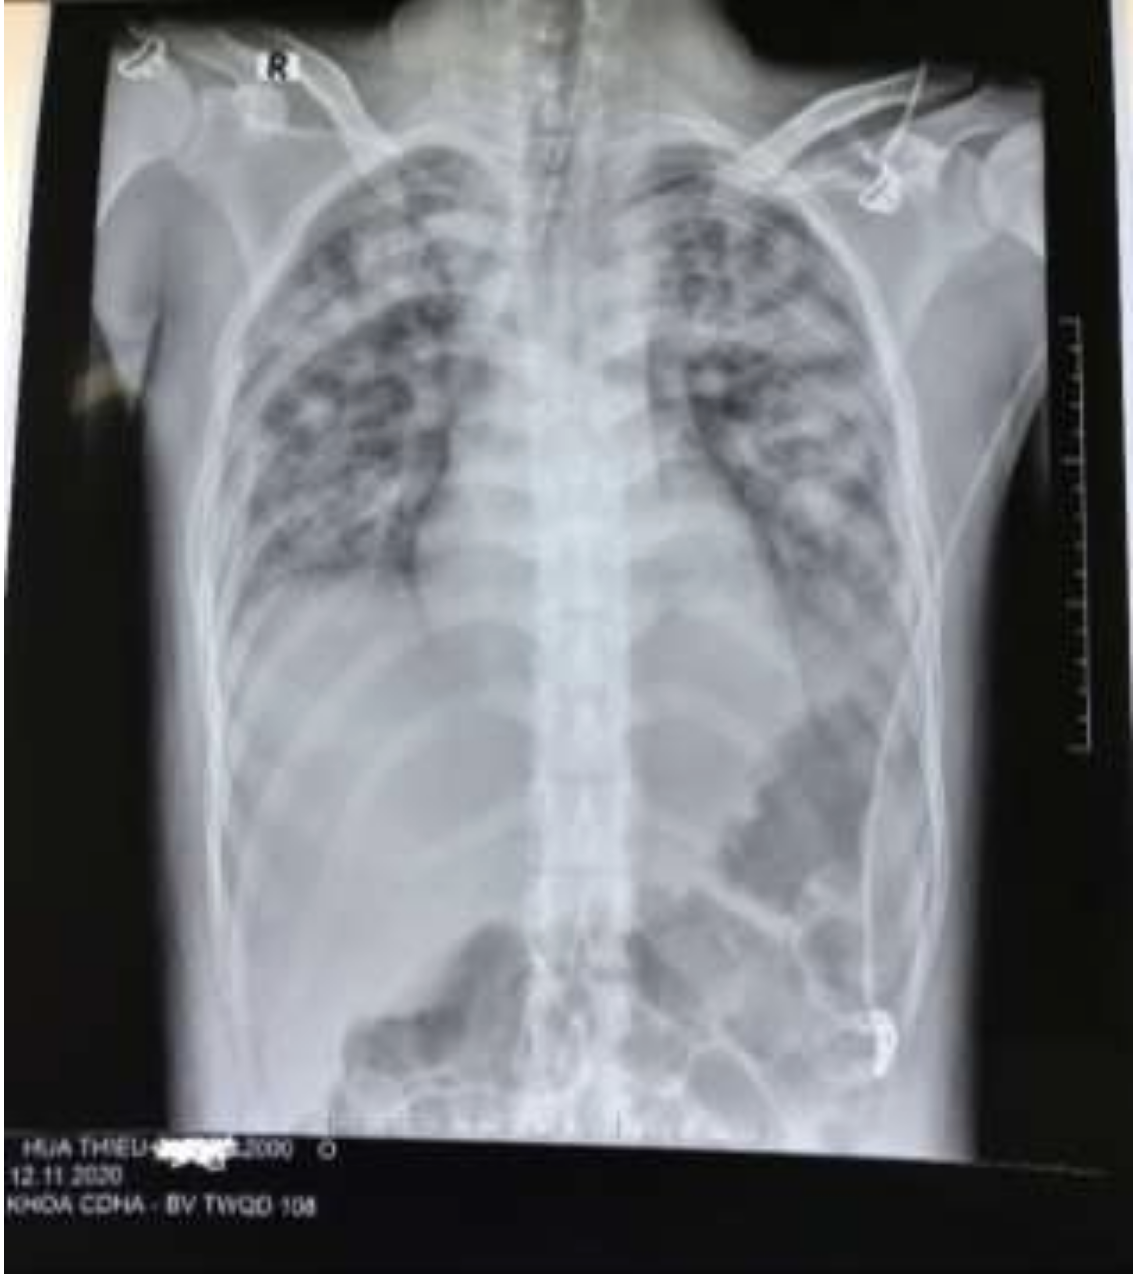

Hình ảnh X-quang ngực thẳng: Mờ lan tỏa 2 phế trường.

Kết quả điều trị, bệnh nhân rút ống nội khí quản sau 3 ngày, hình ảnh tổn thương trên X-quang và tình trạng hô hấp hồi phục gần như hoàn toàn.